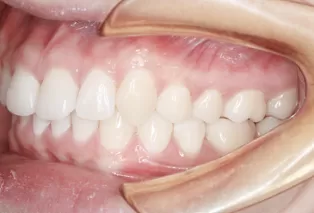

Photos intra-orales après traitement